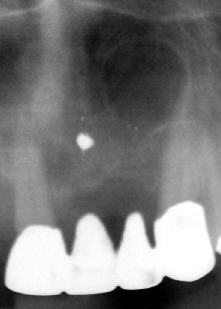

Lange Zeit hatte man nur die Möglichkeit, flache, zweidimensionale Röntgenbilder anzufertigen. Diese reichen auch für viele Indikationen völlig aus und sind seit Einführung des digitalen Röntgens (bzw. der digitalen Bilderstellung) auch deutlich weniger strahlenbelastend als mit konventionellen chemischen Röntgenfilmsystemen. Inzwischen gibt es aber auch in der Zahnheilkunde die Möglichkeit, dreidimensionale Digitale Volumentomogramme (ähnlich einem CT) zu erstellen. Dabei wird die betreffende Region in allen drei Raumebenen dargestellt, so dass man z.B. nicht nur die Knochenhöhe bestimmen kann sondern auch die Knochenkammbreite, oder genau lokalisieren kann, wie ein verlagerter Eckzahn im Kiefer liegt. Außerdem sind DVT's unter Umständen in der Parodontologie (Bifurkations- und Taschendarstellung), der Endodontie (Darstellung des Wurzelquerschnitts mit den Wurzelkanälen), der zahnärztlichen Chirurgie (Lage retinierter und verlagerter Weisheitszähne zum UK-Nervkanal), der Kieferorthopädie (Bestimmung der Zahnbreite noch nicht durchgebrochener Zähne im Verhältnis zur bestehenden Zahnlücke) anwendbar.

DVT eines zahnlosen Unterkiefers in allen drei Ansichten und als 3D-Modellation mit virtuell platzierten Implantaten. Zum Vergrößern mit der Maus über das Bild ziehen (benötigt Javascript). |